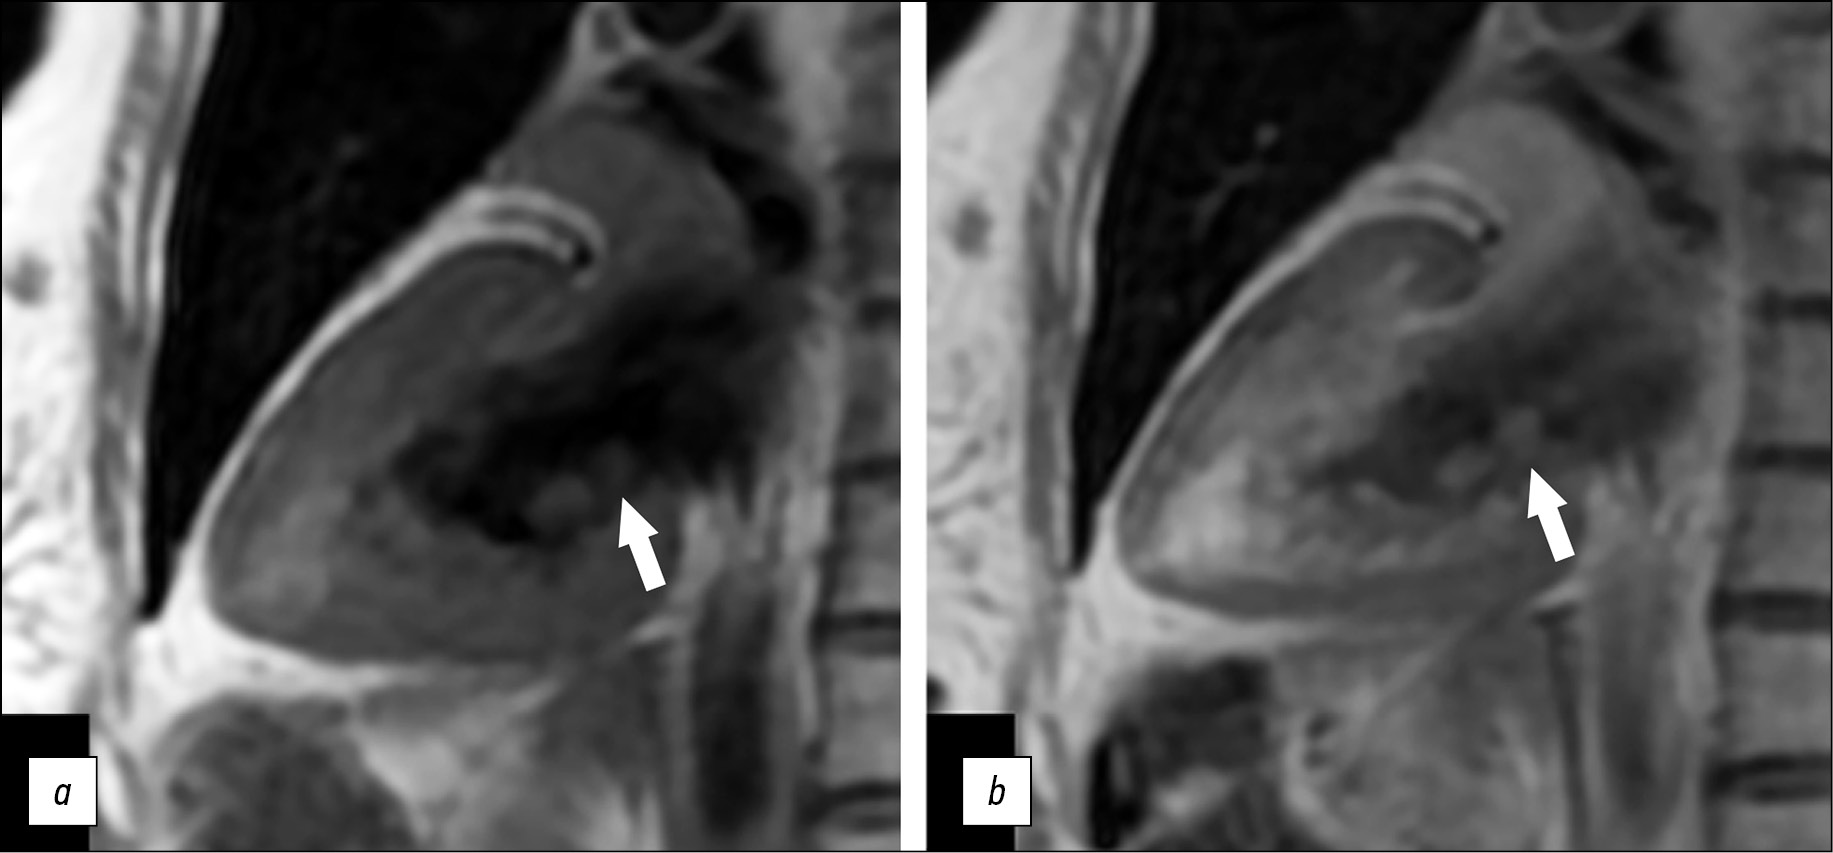

A series of Fiesta-CINE functional examinations in standard axes (two- and four-chamber long axis with 8 mm slice thickness and 0 mm inter-slice interval) was performed after a series of panoramic and axial chest scans in cardiac MRI. Tumor visualization in standard cardiac MRI views was difficult because of the small size of the mass. Optimal mass visualization was obtained in the modified Fiesta-CINE two- and four-chamber views (Fig. 2).

Fig. 2. Magnetic resonance imaging of the heart, two-chamber view: a, left ventricular systolic phase; b, left ventricular diastolic phase. Additional mass on the posterior mitral valve leaflet (black arrows).

A small round-shaped mass (5 × 8 mm in size) on the posterior mitral valve leaflet on the left atrial side was confirmed. The examination was performed before and after early and delayed contrast enhancement using T2 SS, FSE, and FS pulse sequences—T2 WI with signal suppression from blood and adipose tissue—and PS MDE (PSIR), TI 250 ms postcontrast images to obtain tissue mass characteristics. A contrast agent (gadopentetic acid) was injected at 0.2 ml/ kg body weight.